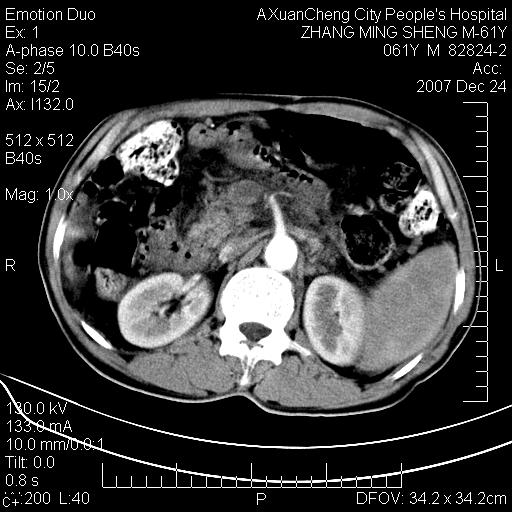

标题: CT11031:M61Y,胰腺占位

大家侃侃门静脉和胆管系统怎么回事,肝内转移?

胰腺癌肝转移

肝硬化,门脉高压,脾肿大;弥漫性肝癌,肝内、门脉、腹膜后淋巴结转移,肝内外胆管扩张,胰头区占位,建议mr检查

胰腺癌伴肝内转移;门脉、肠系膜上v癌栓形成。

考虑为:胰腺癌伴肝脏转移、腹膜后淋巴结转移,门静脉及肠系膜上静脉瘤栓形成。

胰体尾癌伴肝内转移,门静脉及肠系膜上静脉瘤栓形成.